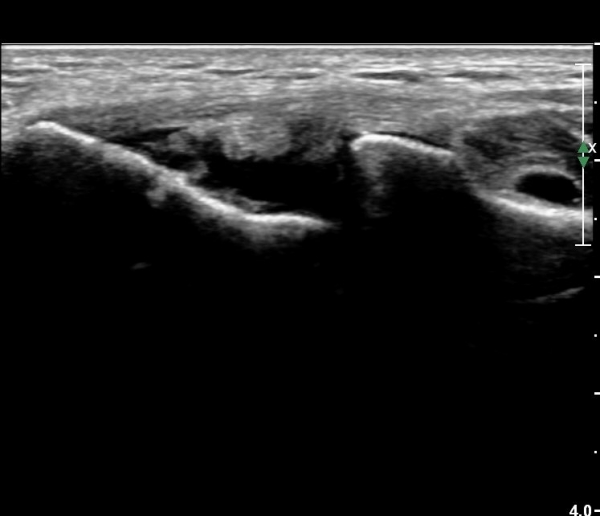

ÃÊÀ½ÆÄ °Ë»ç

ÆÈ²ÞÄ¡ ¾ÕÂÊ ¼ÒµÎ Á¾´Ü¸é°Ë»ç¿Í Ⱦ´Ü